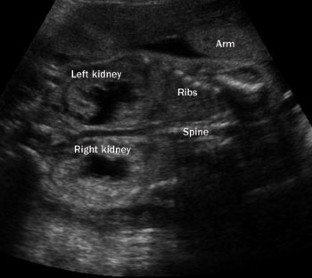

Johnson, M. P. et al. Sequential urinalysis improves evaluation of fetal renal function in obstructive uropathy. Am. J. Obstet. Gynecol. 173, 59–65 (1995).

Nicolini, U. et al. Further predictors of renal dysplasia in fetal obstructive uropathy: bladder pressure and biochemistry of 'fresh' urine. Prenat. Diagn. 11, 159–166 (1991).

Nicolaides, K. H., Cheng, H. H., Snijders, R. J. & Moniz, C. F. Fetal urine biochemistry in the assessment of obstructive uropathy. Am. J. Obstet. Gynecol. 166, 932–937 (1992).

Evans, M. I. et al. Sequential invasive assessment of fetal renal function and the intrauterine treatment of fetal obstructive uropathies. Obstet. Gynecol. 77, 545–550 (1991).